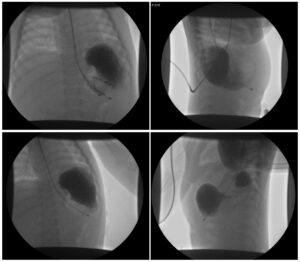

Incarcerated Gastric Volvulus and Splenic Herniation. Upper GI. Unannotated. JETem 2025